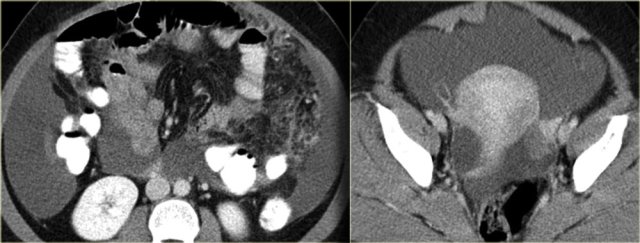

In peritoneal carcinomatosis we see tumor nodules along the peritoneal lining (arrow), omental tumor deposits, and bowel obstruction.

Pseudomyxoma peritonei is the result of a mucinous adenocarcinoma of the appendix, which presents as a mucocele and spreads to the peritoneal cavity.

It is a clinical syndrome, characterized by recurrent and recalcitrant voluminous mucinous ascites due to surface growth on the peritoneum without significant invasion of underlying tissues.

A typical feature of pseudomyxoma peritonei is scalloped indentation of the surface of the liver and spleen.

Unlike peritoneal metastases, there are no tumor nodules.

There may be some calcifications.

On the left another case of pseudomyxoma peritonei.

There is hardly any scalloping of the liver.

Notice the thickened falciform ligament.

There is a mucocele of the appendix (arrow).

This finding is only rarely seen.

There is compression of the mesentery resulting in a thickened cake-like hyperdense mesentery (arrow).

There are also some calcifications.

Pseudomyxoma peritonei is often confused with mucinous carcinomatosis.

Unlike carcinomatosis it does not have true omental tumor deposits presenting as omental cake or peritoneal tumor deposits.